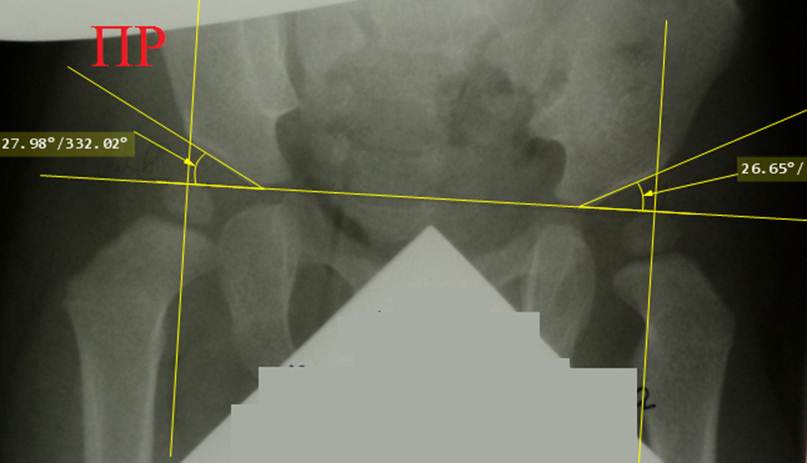

Снимок

ребенка 7 месяцев, расчерчивание по Хильгенрейнеру. Двухсторонняя дисплазия

тазобедренных суставов с децентрацией: обратите внимание на вертикальные и

горизонтальные позиции, ацетабулярные углы

и положение ядер окостенения головок относительно линий Омбредана - Перкинса.

Постановка диагноза запоздалая. Назначено консервативное лечение с помощью

отводящей шины БелНИИТО (она применяется

редко и не имеет преимуществ перед другими).

Тот

же ребёнок. Уже через неделю ортезирования ножки приняли положение Лоренц I. Сделан снимок с ортезом: оси шеек обеих бедер чётко

направлены в центр вертлужных впадин, подтверждено вправление головок обеих

бедер. Использование ортеза продолжено

еще 3 месяца.

Предыдущий

снимок мы специально расчертили по

Хильгенрейнеру: показатели центрации головок не в норме, хотя ядра окостенения

находятся кнутри от линий Омбредана – Перкинса. Потому не следует применять

схемы Хильгентейнера и Рейнберга для определения центрации головок на снимках в

ортезе.